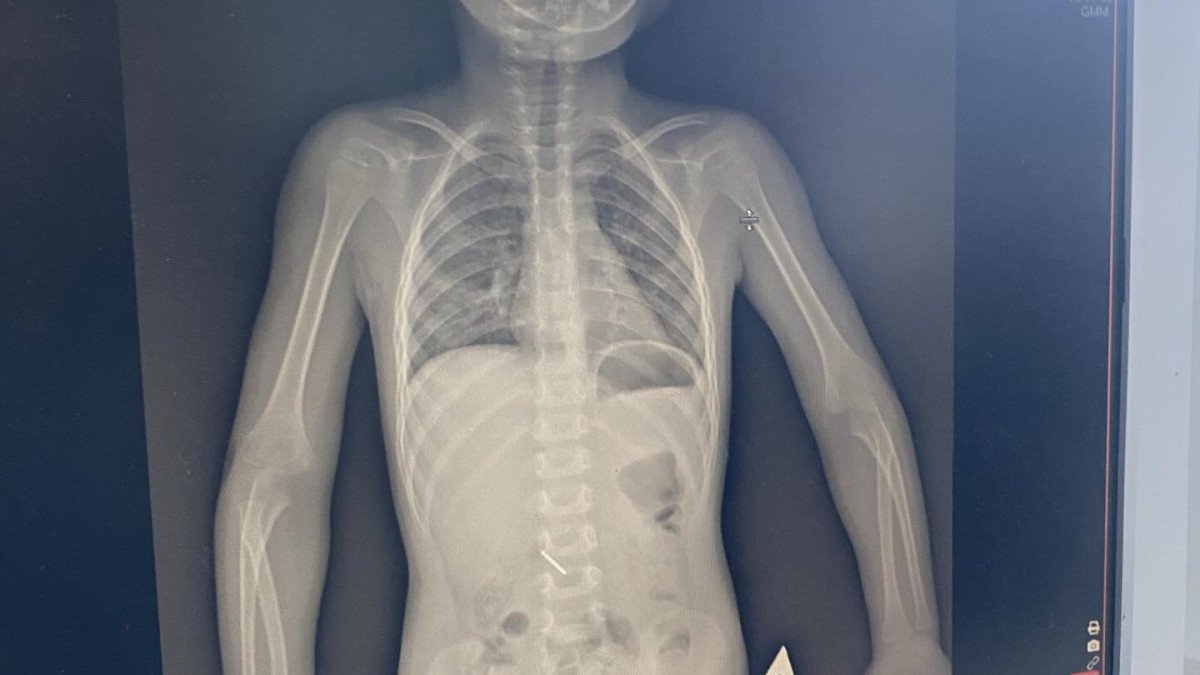

Оның айтуынша, тісін емдеу кезінде бала стоматологиялық бұрғыны (бор) жұтып қойған.

Бірнеше күн ішінде бала екі рет рентгенологиялық зерттеуден өтіп, хирург қарауында болған және оған ФГДС (фиброгастродуоденоскопия) процедурасы жасалған.